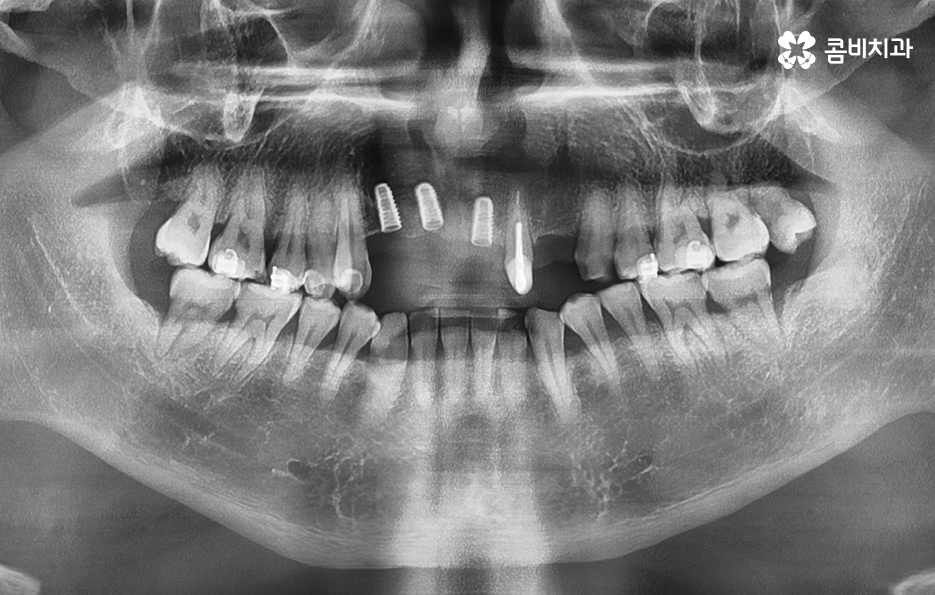

이렇게 앞니가 상실되면 심미적, 기능적 불편이 크기 때문에 많은 분들이 앞이빨 임플란트 과정을 거치게 되는데 앞니 임플란트는 어금니와는 다른 부분에서 좀더 정교한 치료가 필요하며 앞니 부위는 뼈가 얇고 심미성이 중요한 부위라는 점에서 잇몸 라인, 앞니의 각도, 심미성, 주변 치아와의 조화까지 모두 맞아야 자연스럽게 보이므로 정교한 치료의 중요성이 더 높은 부위라고 할 수 있어요

그리고 앞니는 씹는 힘이 약해 보이지만 가로 방향 힘이 많이 가해져서 임플란트에 부담을 주기 쉽고 앞니 상실의 원인이 치주염이라면 뼈가 많이 녹아 있는 경우가 많아 뼈 이식이 필수적인 상황이 자주 생기므로 앞이빨 임플란트 과정에서 주의해야 할 점들에 대해 잘 알고 접근하는 것이 중요한 거예요

또한 앞니는 잇몸의 모양이 심미성에 큰 영향을 주는데, 잇몸이 얇으면 임플란트가 비쳐 보이거나 잇몸 라인이 붕괴될 위험이 있어서 이런 경우에는 잇몸 두께를 보강하는 잇몸 이식술이 필요할 수 있으며 앞이빨 임플란트 과정 뿐 아니라 치료 후에도 잇몸 관리는 앞니 임플란트의 수명, 심미적인 유지에 있어서 중요한 요소라고 볼 수 있었어요

앞니는 사람들에 따라서 상실 원인이 다르고 현재의 잇몸 및 전신건강 상태가 다르며 특히 중년이후에는 기존의 보철물이 노후되거나 치주염으로 인해 치아를 상실하는 경우도 많기 때문에 앞이빨 임플란트 과정이라서 해서 단지 빠르게 치료하는 것만이 중요한 것이 아니라 장기적인 안정성 등을 충분히 고려한 치료 계획이 중요하므로 경험 많은 치과의사와 충분히 상의하고 정밀검진 결과를 토대로 나에게 맞는 치료 계획 그리고 사후관리까지 고려한 장기적인 유지까지 고려하여 판단하시길 바라고 있어요